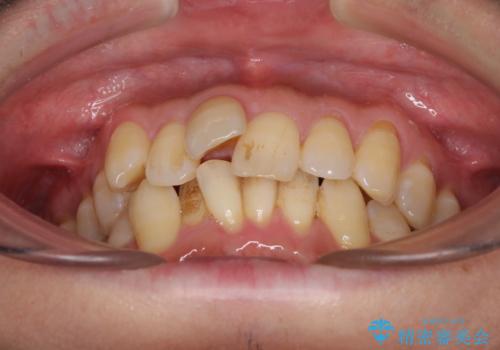

前歯のデコボコ ワイヤー装置での短期間治療

- 前歯のデコボコを気にして来院された患者様です。

インビザラインまたはワイヤー装置、どちらでも対応可能でしたが、自己管理の少なさ、期間の短さから、ワイヤー装置による矯正治療を行うこととしました。